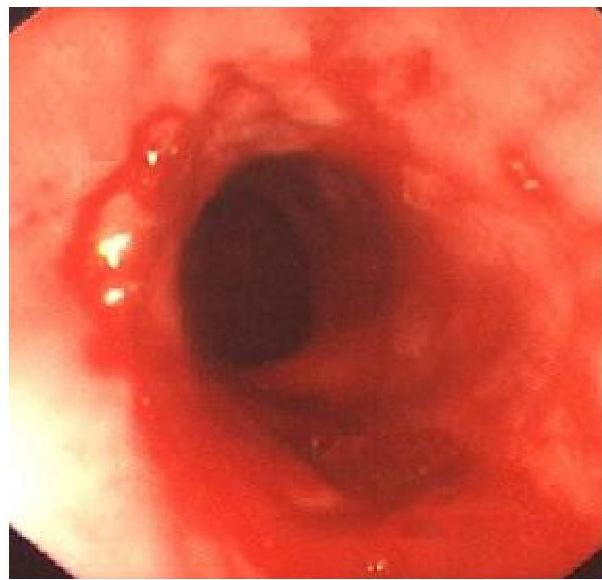

Other Diagnostic Procedures

- Endoscopy (with biopsy): To look for erosions or ulcer of esophagus

- Endoscopic appearance

- Histological findings